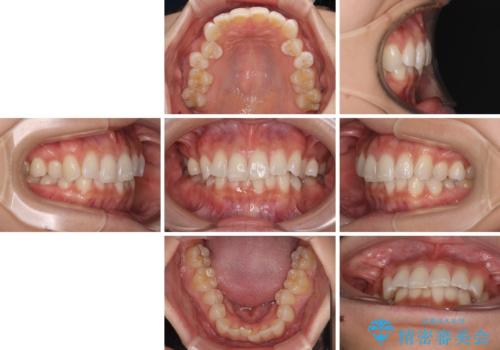

- 上下前歯のデコボコとディープバイトを気にして来院された患者様です。

歯列全体に叢生があり、舌の突出癖が認められたため、突出癖が改善されない場合には口元が突出するリスクが考えられました。